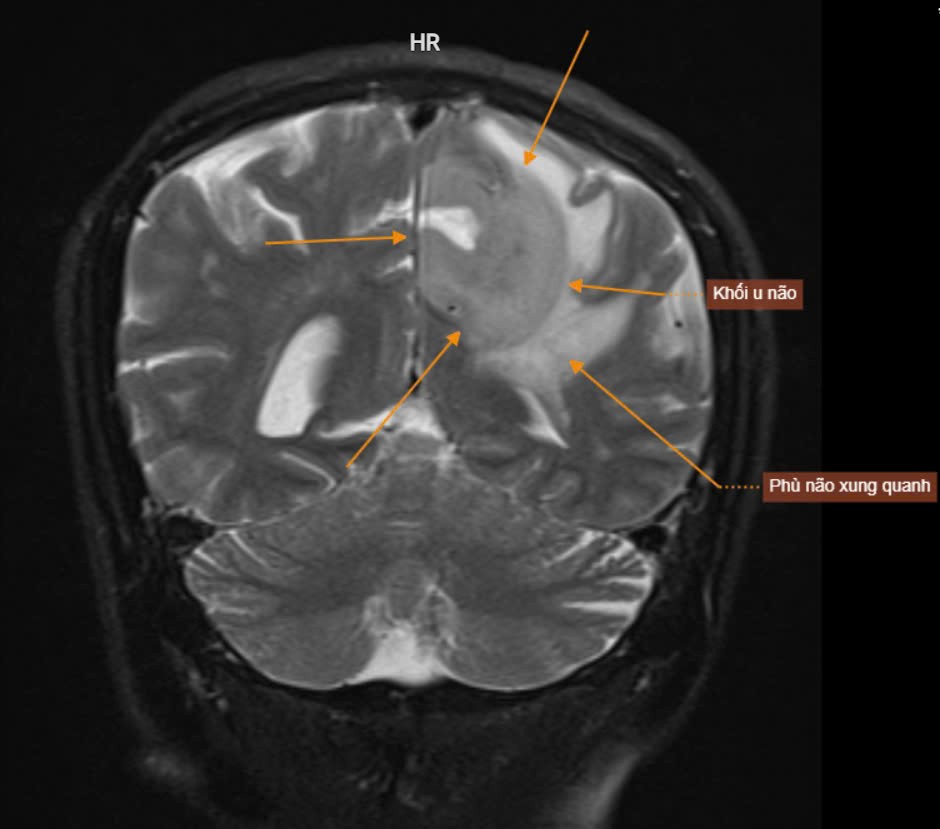

Ngày 13/12/2024 Bệnh viện Thái Bình đã tiếp nhận bệnh nhân B.T.T 71 tuổi, đến khám với triệu chứng, đau ngực, tăng huyết áp, đau đầu âm ỉ